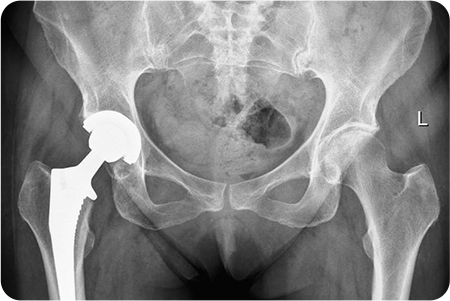

고관절 관절염

인공관절치환술

관절염으로 닳아버린 대퇴골두와 관골구를

정밀하게 절제합니다. 다리 길이와 관절 정렬을 맞추고,

움직임이 부드럽고 안정적인지 확인한 뒤 봉합

합니다.